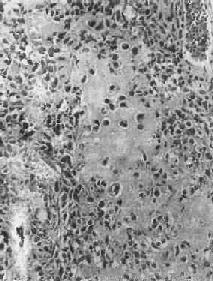

图17-7 硬化性骨肉瘤 股骨干骺端呈梭形肿大,骨干被包埋于中央,周围有清晰的放射状骨梁 骨肉瘤的切面呈多彩状,其外观取决于肿瘤性骨质及软骨的含量以及出血、坏死等继发改变的程度。例如,肿瘤性骨质成分较多时则肉眼观呈黄白色,质地坚硬,有砂粒小点或条纹;如软骨形成明显时则呈半透明状;在肿瘤细胞丰富部位则呈灰红色鱼肉状。 镜下,骨肉瘤由明显间变的梭形或多边形肉瘤细胞组成,细胞大小不等,核形奇异,大而深染,核仁明显,易见病理性核分裂像。肿瘤细胞直接形成肿瘤性类骨组织或骨组织,是诊断骨肉瘤的最重要的组织学依据。所形成的类骨组织或骨组织在不同肿瘤或同一肿瘤的不同部位多少不等。往往可看到肿瘤性骨质发生过程中各阶段的形态,最早期在恶性肿瘤细胞间出现均质红染的胶原样物质,其后红染物质逐渐增多,将肿瘤细胞分隔疏远,构成小梁或片状的肿瘤性类骨组织(图17-8)。类骨组织可伴钙盐沉着,其内的肿瘤细胞固缩变小,形成肿瘤性骨质。骨肉瘤内也可出现肿瘤性软骨(图17-9)。

图17-8 骨肉瘤

图17-9 骨肉瘤 骨肉瘤起源于间叶细胞,形态上表现出多方向分化的潜能,而使骨肉瘤的成分较为复杂。根据其主要的分化成分,组织学上可分成几种类型:最常见者为骨母细胞型,以异型骨母细胞为主要成分,细胞呈多边形,较肥硕,核圆、核仁明显,胞浆丰富,伴较多的肿瘤性类骨和骨组织形成;由软骨肉瘤样组织为主要成分者,属软骨母细胞型;以梭形细胞和胶原纤维为主,似纤维肉瘤者为纤维母细胞型;肿瘤内有许多显著扩张的血管腔隙,伴较多破骨细胞型多核巨细胞,甚似动脉瘤性骨囊肿者为血管扩张型,此型十分少见。在同一肿瘤中上述各种类型的成分常混合存在,但以某一类型为主。不论何种类型,都能见到肿瘤细胞直接形成肿瘤性类骨和骨组织,这是区别于其他骨肿瘤的特征。 【临床病理联系】 骨肉瘤最早的症状是局部疼痛,日渐加剧,持续不断,以夜间为明显。发病2~3月后,局部出现肿胀、质地坚硬。患部皮肤紧张,多呈紫铜色,表面静脉曲张。如骨皮质受侵犯时,轻度外伤即可致病理性骨折。 血清碱性磷酸酶的增高是骨肉瘤的唯一重要化验室检查指征,这和瘤组织内碱性磷酸酶的含量增高相一致,约见于半数病例,对骨肉瘤诊断和推测预后有一定价值。 X线检查对骨肉瘤的诊断有重要价值。常见到肿瘤性骨质形成,表现为云絮状或斑块状密度增高的阴影。这类病例在X线诊断时称为硬化型骨肉瘤。少数病例呈溶骨型,病理上主要为软骨母细胞型和纤维母细胞型以骨质破坏为主,呈虫蚀状或大片状骨质破坏,边界模糊。如前所述,X线检查如发现Codman三角或日光放射状阴影,则对骨肉瘤的诊断很有帮助。 骨肉瘤是高度恶性肿瘤,一般生长迅速,预后较差。局部扩展一方面侵犯骨髓腔及骨皮质,并破坏骨膜及周围软组织;另一方面向骨骺蔓延,甚至扩展到关节软骨。极少数病例可越过关节软骨,侵入关节囊,造成关节活动障碍。近年还发现,骨肉瘤在骨内可呈跳跃性转移(skip metastasis),即在与原发瘤同一骨内的另一处形成孤立性转移结节,甚至还可以转移到相邻的骨内,形成孤立结节,约见于1/4的病例,且不易被X线检查发现,因而预后更差。远处转移多经血道到肺,不少病例在发现原发瘤的同时,即已有肺转移。极少数病例可转移到局部淋巴结。 皮质旁骨肉瘤是骨肉瘤的一种特殊亚型。与一般骨肉瘤不同,本瘤发生于骨膜或骨旁的成骨性纤维组织,瘤体的主要部分位于骨的表面。大多生长缓慢,恶性程度较低,预后远较一般骨肉瘤好,其发病年龄比一般骨肉瘤大5~10岁。本瘤好发于股骨下端的后方,其次为股骨上部。瘤体一般较大,边界较清晰,可呈分叶状。早期对骨质侵犯较少,故易于剥离;晚期可破坏骨皮质而侵犯骨髓腔,但远处转移少见。在切面上,靠近骨皮质或骨膜部分质坚实,而瘤体边缘部分较软,为富于瘤细胞部分。瘤体一般不见出血及坏死。镜下,为分化好的骨肉瘤,成骨现象比较明显。在肿瘤性骨小梁间为增生较活跃的纤维组织,间变不明显,形态上似分化好的纤维肉瘤。少数皮质骨肉瘤分化较差,形成骨质较少,与骨内骨肉瘤相似。